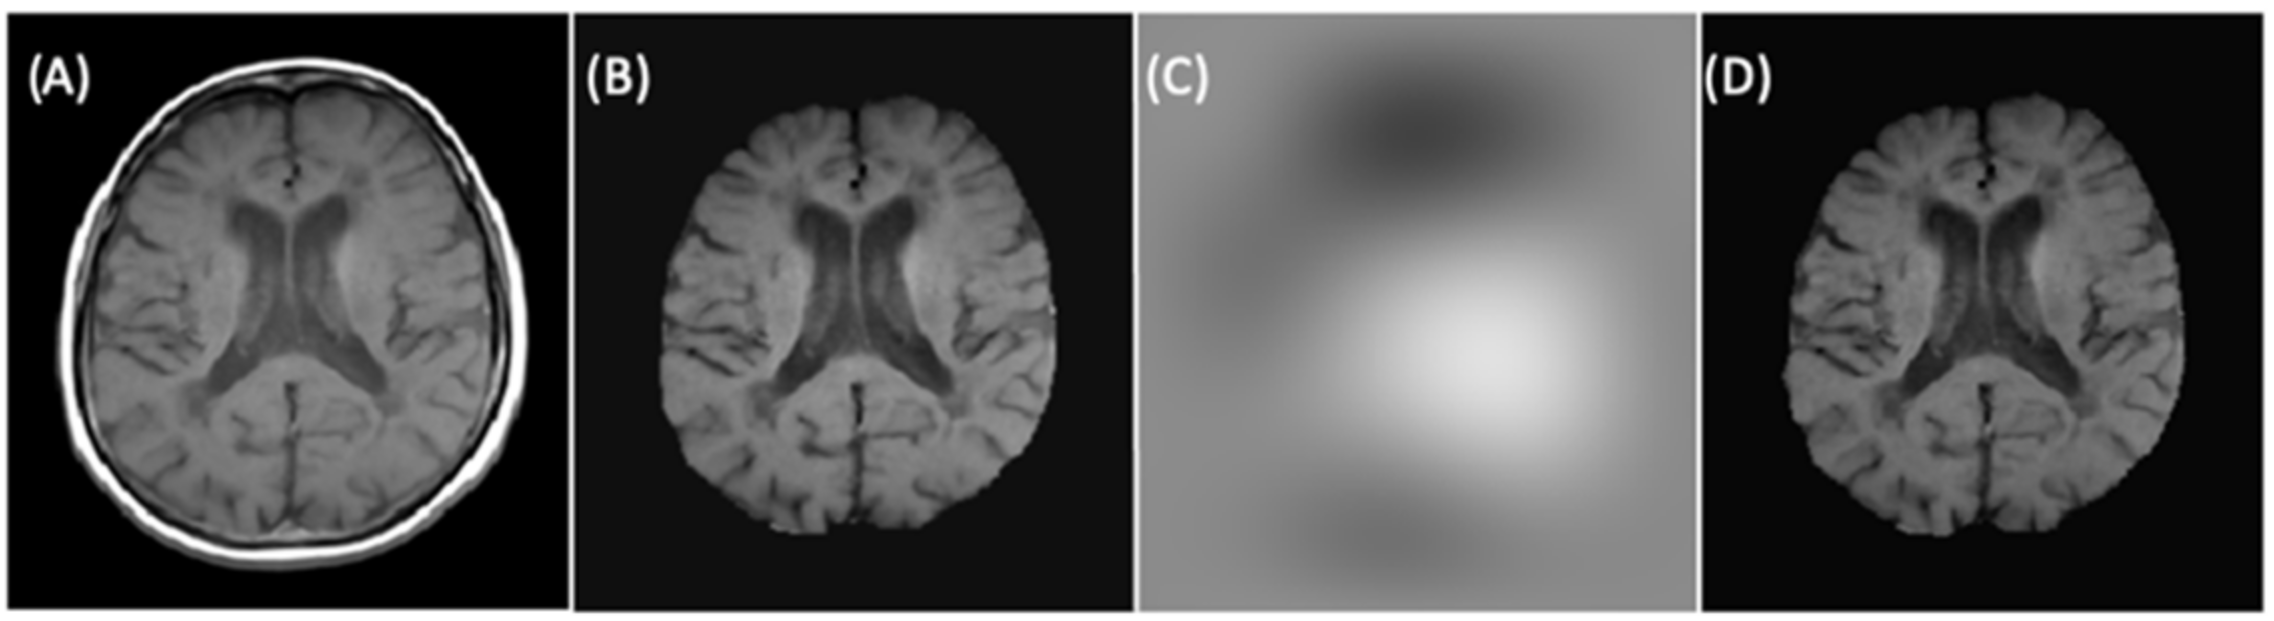

Finally, to improve the signal intensity variability in MRIs caused by magnetic field inhomogeneities, we applied the image bias correction filter (N4ITK) in step six of the preprocessing after automatic brain extraction. Figure 6 illustrated an example of a slice with the application of the bias correction step. The brain extraction process and bias correction were applied to all the slices in the exam (each patient), and we were able to see the volumetric representation of the extracted brain (see Figure 7).

Figure 6.

(A) Rigidly registered image. (B) Skull-stripped image. (C) Bias correction filter. (D) Final image.